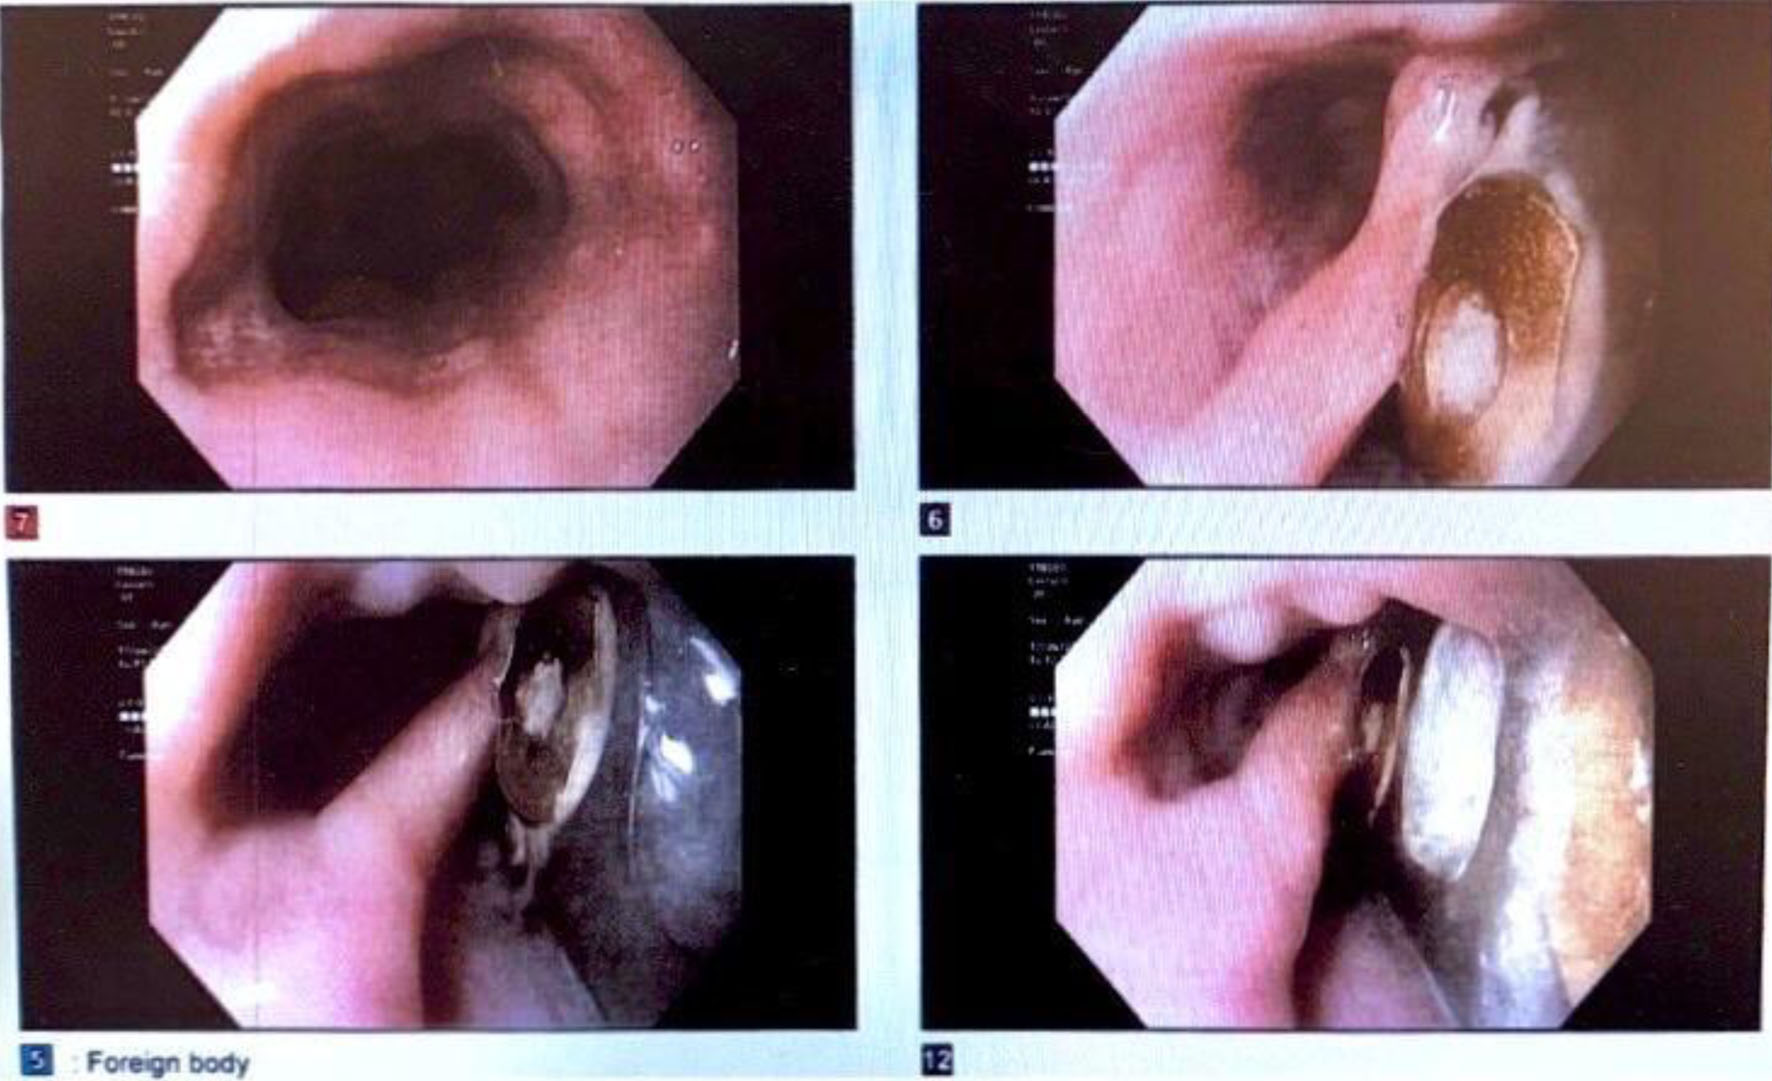

One month later, the patient underwent removal of the cervical spine hardware and a surgical repair guided by EGD (Fig. 4) with muscle flap reinforcement (Fig. 5). A feeding gastrostomy tube was placed and both the procedure and postoperative period were uncomplicated. The patient was discharged 6 days after surgery with a JP drain and gastric tube feedings.

![]() Click for large image | Figure 4. Esophagogastroduodenoscopy 12 months postoperatively. Image displays the cervical hardware, which had eroded through the posterior wall of the cervical esophagus concordant with the esophagram, which had demonstrated contiguity between the lumen of the esophagus and the cervical hardware based on the transit of the oral contrast, consistent with a posterior esophageal wall perforation contained by the cervical hardware without extravasation. These findings were also consistent with the patient’s chronic presentation without sepsis. |